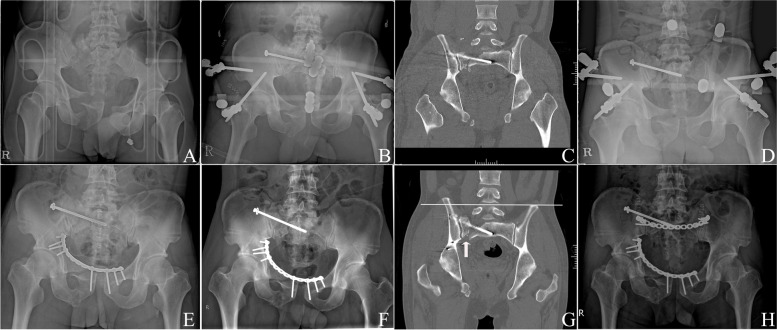

In both groups, fracture union was achieved in all the patients. Three patients experienced delayed union, one from the plate fixation group (7.1%) and two from the IS screw fixation group (3.2%). In the IS screw group, 3 patients (4.8%) developed postoperative nerve injury, which was not observed in the plate group, although no significant differences were noted between the two groups (p > 0.999). Revision surgery for a screw change was performed in only one patient because of a screw breach to the sacral foramen, and the other two patients did not undergo screw change after confirming the absence of screw malplacement on postoperative CT. None of the groups experienced vessel injury. Five patients (7.9%) in the IS screw group experienced implant loosening, but none in the plate group (p = 0.578). Three of the five patients required revision surgery, two patients required additional posterior plate fixation (Fig. 4), and one required additional IS (S2) screw fixation; in two patients, no other interventions were performed as fracture union was achieved, and no additional interventions were required. One patient in each group developed surgical site infection. In the plate group, the infection was deep and was successfully treated with surgical debridement and antibiotics, while one patient with a superficial infection in the IS screw fixation group recovered after receiving intravenous antibiotics.

Fig. 4.

A A 30-year-old man with a Tile C-type pelvic ring injury. B External fixation and iliosacral (IS) screw fixation on the day of injury. C Coronal reconstructed image showing a well-reduced posterior ring. D Post-injury radiograph at 4 weeks showing IS screw loosening. Definitive treatment was delayed due to unstable conditions of the patient with multiple trauma including aortic dissection. E Anterior plating 1-month post-injury. F Pelvic radiograph showing IS screw migration at 8 weeks post-injury. G Coronal image at 8 weeks post-injury showing vertically displaced sacral alar (arrow) and upward migration of right pelvis (white line). H Posterior transiliac plating was performed to acquire a more rigid fixation at 2 months post-injury